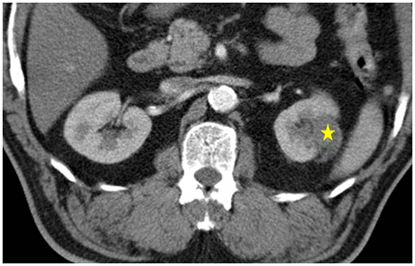

在電腦斷層導引下,將冷凍探針經過皮膚插到腫瘤組織中。冷凍探針在針尖可形成一圓型的超低溫範圍,當溫度低於-20℃即可造成細胞壞死,達到治療目的。因冰塊在電腦斷層下清晰可見,因此可確認治療範圍完全涵蓋腫瘤,且未傷害正常組織。冷凍治療具有包括侵入性極小,無痛,可保留腎功能等好處,於2006年通過衛生署認證,已證實為一安全有效的腎臟腫瘤治療方法。

治療後三個月,以電腦斷層追蹤為主,有時會用超音波或磁振造影的方式追蹤。若有殘存或復發的腫瘤則可重複接受此方法治療。

原則上腫瘤小於4公分,此治療可達到完全根除的效果。若腫瘤太大,可以此治療部份消除,也可於施行多於一次的治療以達根除效果。